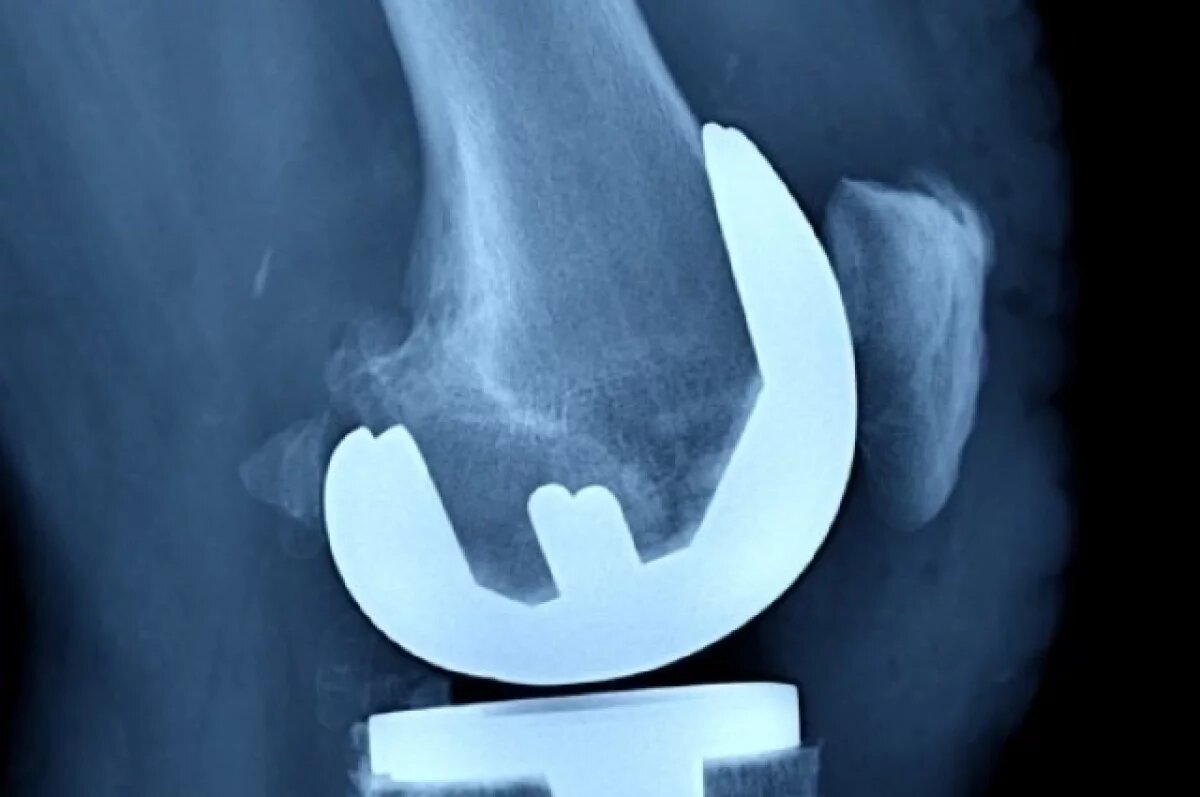

На соревнованиях по самбо Вячеслав Кочугов, победитель первенств Европы и России и призер Кубка мира, получил серьезную травму коленного сустава. Состояние усугублялось сдавливанием малоберцового нерва соединительной тканью, что потребовало сложной операции.

По данным врачей, в ходе хирургического вмешательства специалистам пришлось освободить нерв от спаек, чтобы восстановить его функции. Одновременно с этим были проведены операции по реконструкции трёх связок коленного сустава: коллатеральной, передней и задней крестообразных.

Травматолог Алексей Крупко подчеркнул, что медикам удалось сохранить собственное сухожилие подколенной мышцы спортсмена. Врач рассказал, что оно было оторвано, но отлично дотягивалось до точки крепления и было надёжно зафиксировано.

По словам специалистов, естественная стабилизация коленного сустава полностью восстановлена.

Врачи считают, что после завершения реабилитационного курса Вячеслав Кочугов сможет вернуться к профессиональной спортивной деятельности.